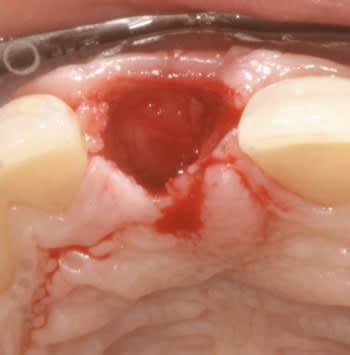

Ci joint cas avec membrane résorbable laissée exposée volontairement ( technique Bio coll proposée par Anthony G. Scar dans les années 2000 remis au gout du jour par tarnow en 2006 ).

Celà ne marche pas avec toutes les membranes...

fig 3 exo

fig 4 pose membrane résorbable + os xénogène

fig 5 membrane suturée